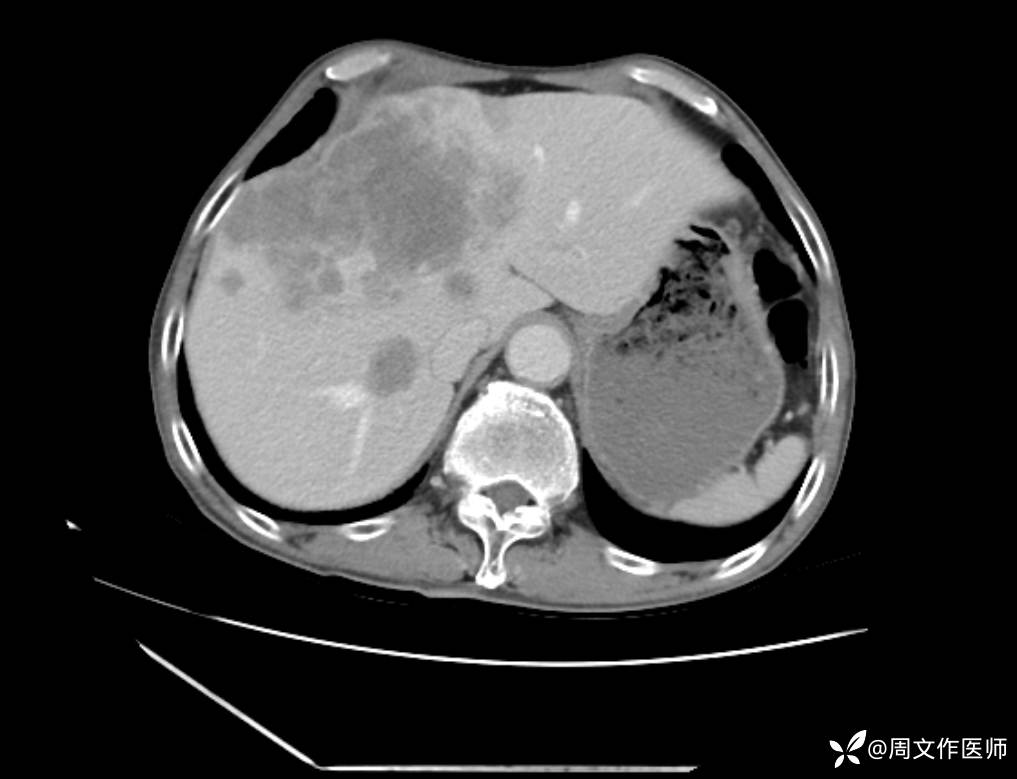

腹部增强CT检查